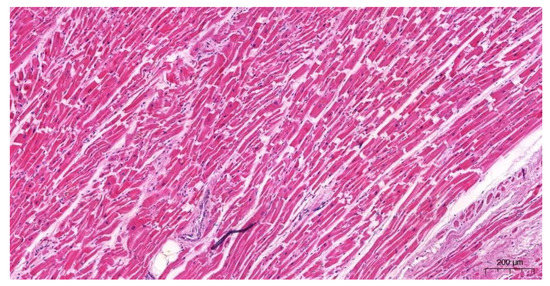

2.2.3. The Microscopic Examinations